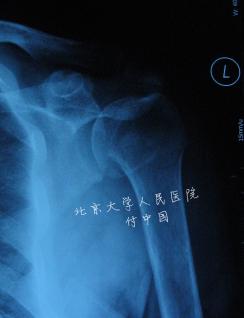

两部分解剖颈骨折